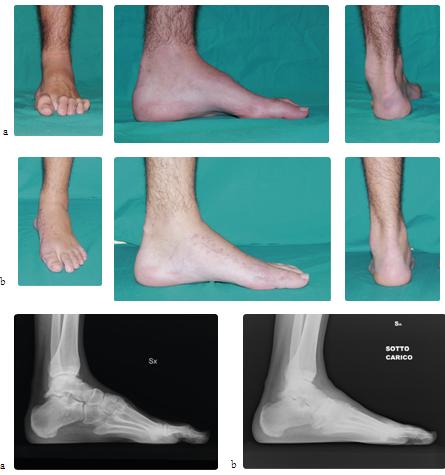

Caso 5: Piede piatto dell'adulto

Maschio, 66 anni, grave deformità del retropiede secondaria a piede piatto non trattato (a). Sottoposto a intervento di artrodesi della sottoastragalica secondo Grice e allungamento del tendine di Achille. Il controllo a 8 mesi di distanza dall'intervento mostra il ripristino dell'arco plantare, del fisiologico allineamento del calcagno e del rapporto astragalo-scafoideo (b).